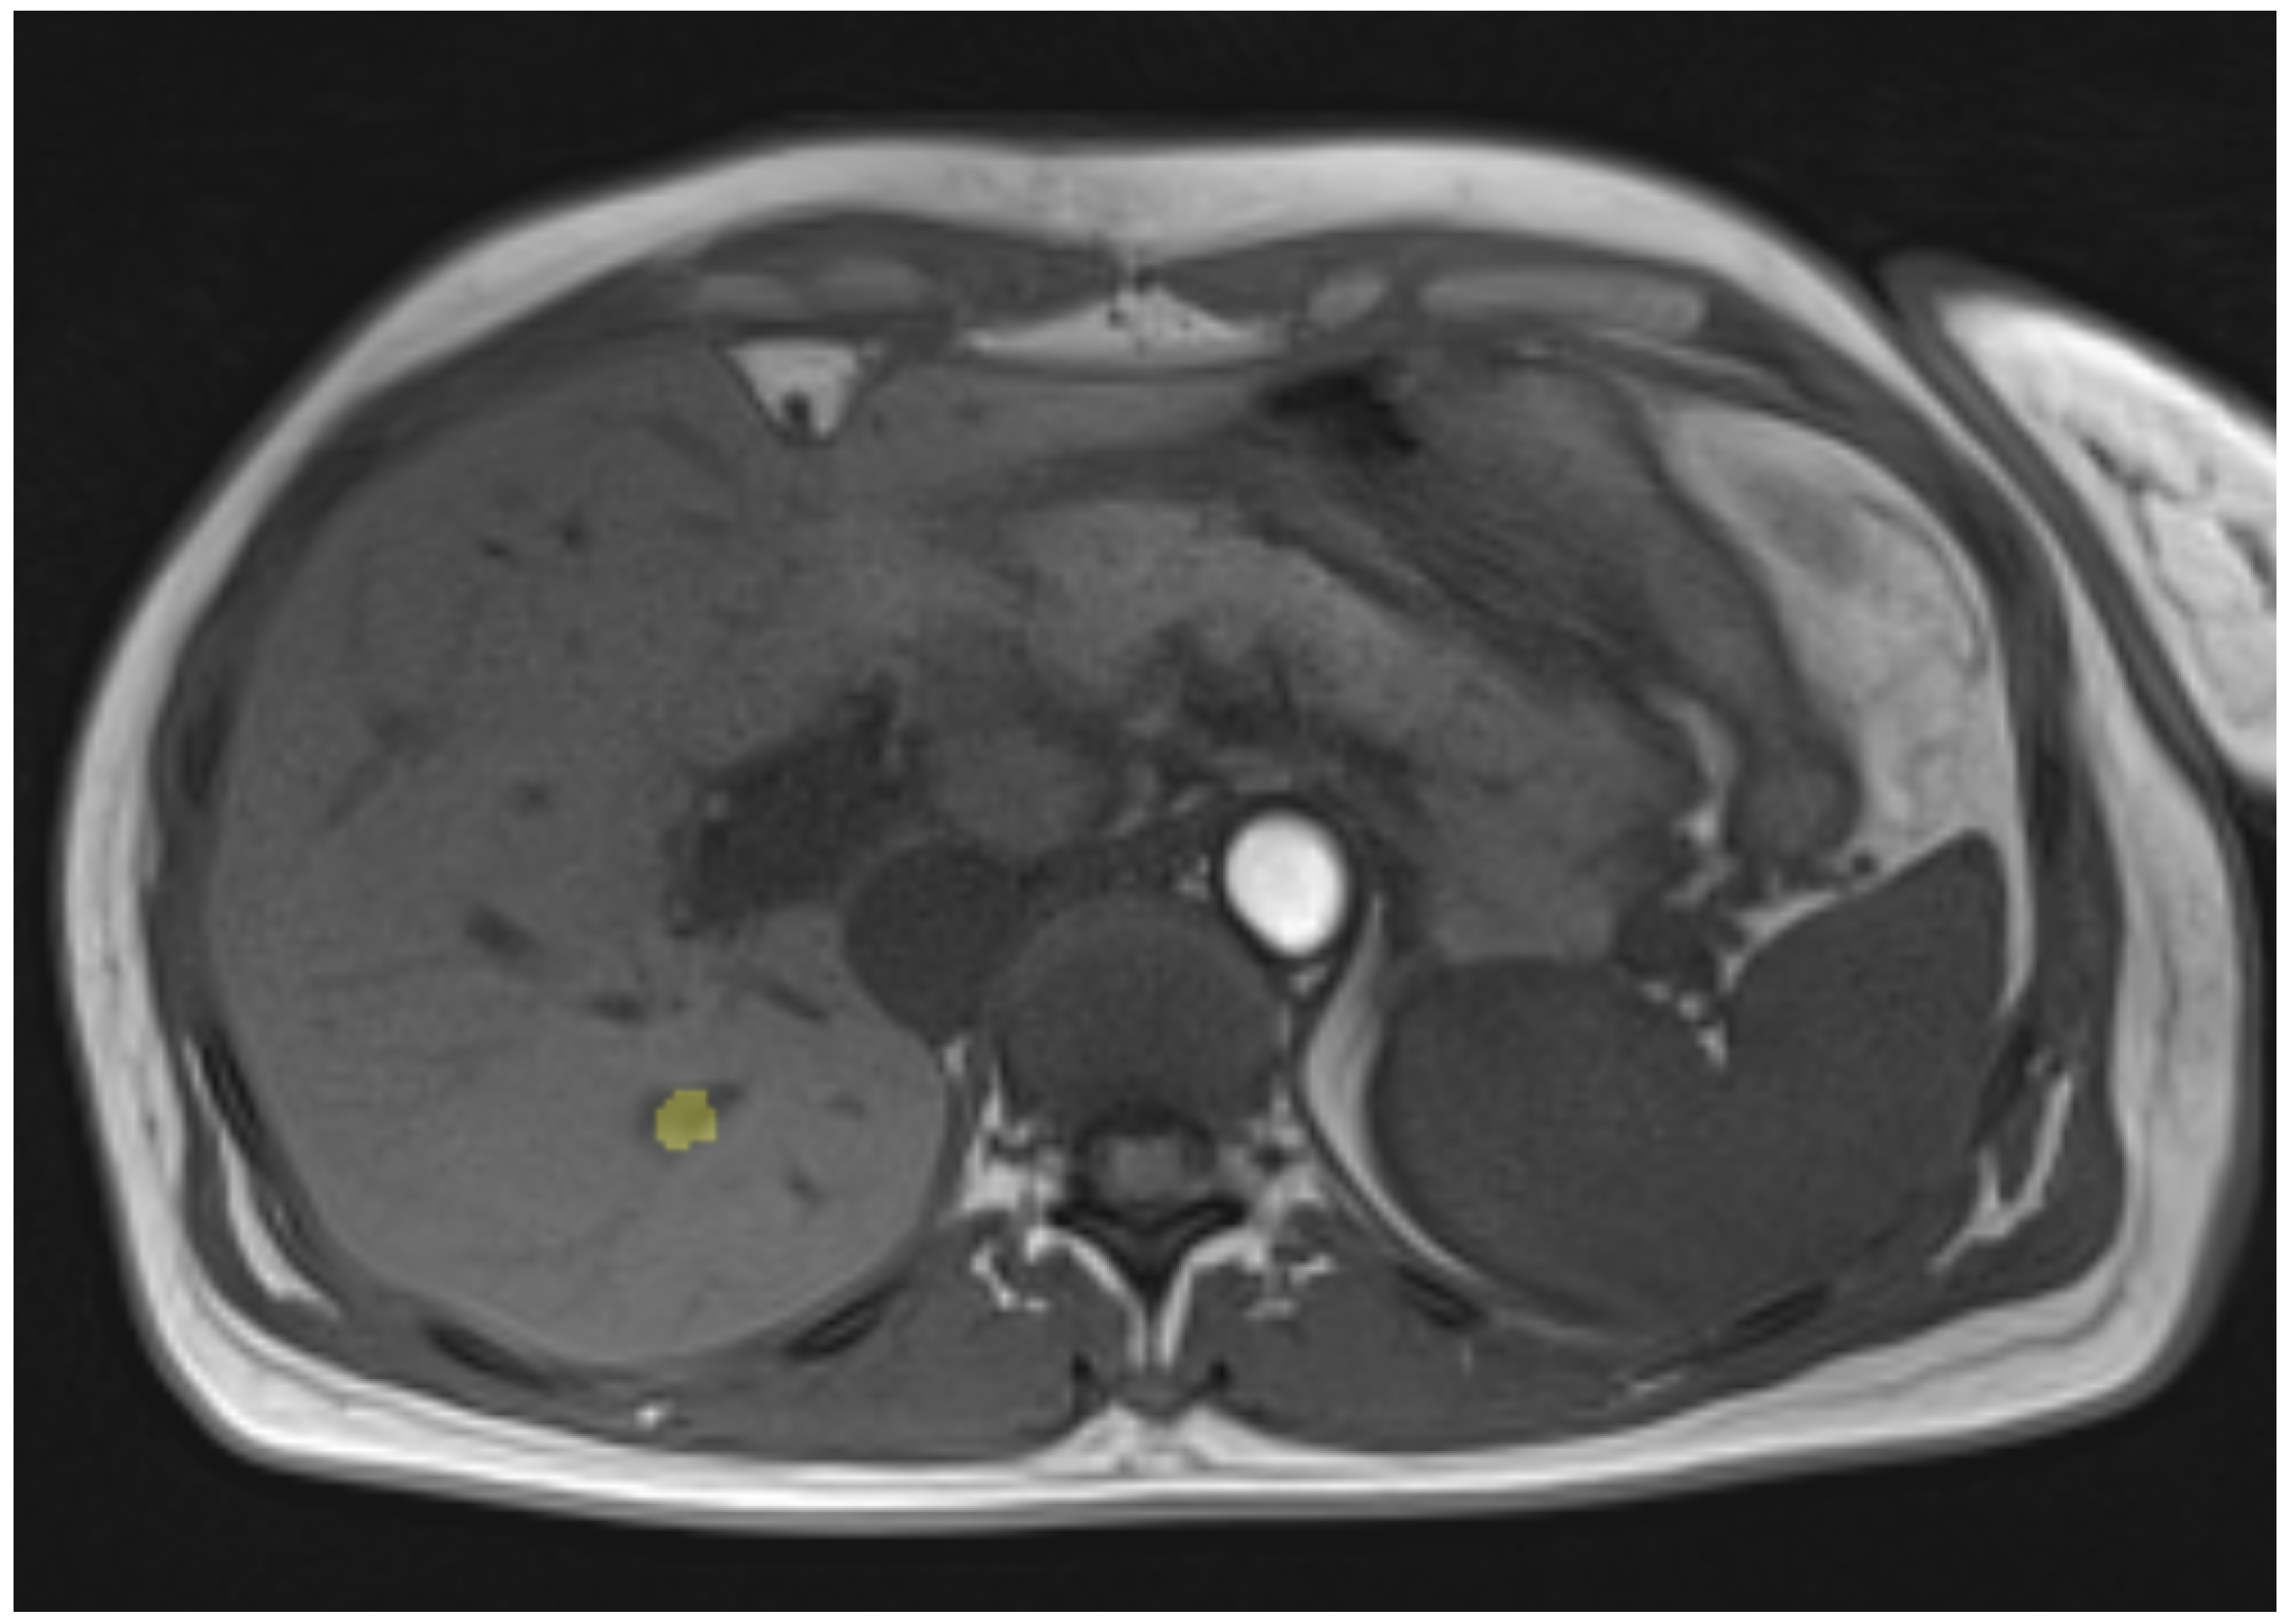

3.2. Clinical Case